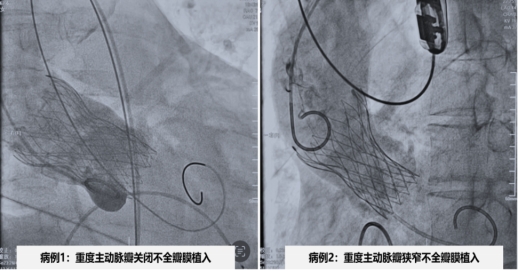

病例1为女性,反复胸闷胸痛气促不适1年余,入院后心脏超声提示左房增大,室间隔增厚,升主动脉略增宽,主动脉瓣瓣膜重度返流,瓣叶轻微增厚,无钙化。患者因药物治疗效果不佳,经术前检查评估及多学科充分的术前讨论后行微创介入瓣膜置换术,并成功植入TaurusElite AV29瓣膜。术后超声结果显示,瓣膜工作正常,血流动力学良好,术后第二天由ICU病房转入普通病房。病例2为男性,近10天来间断胸闷气促不适,入院后心脏超声提示主动脉瓣二叶瓣畸形、钙化伴及重度狭窄,左室壁增厚,左心收缩功能减退,跨瓣压差107mmHg。入院后检查评估及多学科充分评估有手术瓣膜置换指征,在多学科讨论后行微创介入瓣膜置换术,顺利植入TaurusElite AV26瓣膜。术后超声结果显示,跨瓣压差降至8mmHg,手术取得圆满成功。术后第二天由ICU病房转入普通病房。